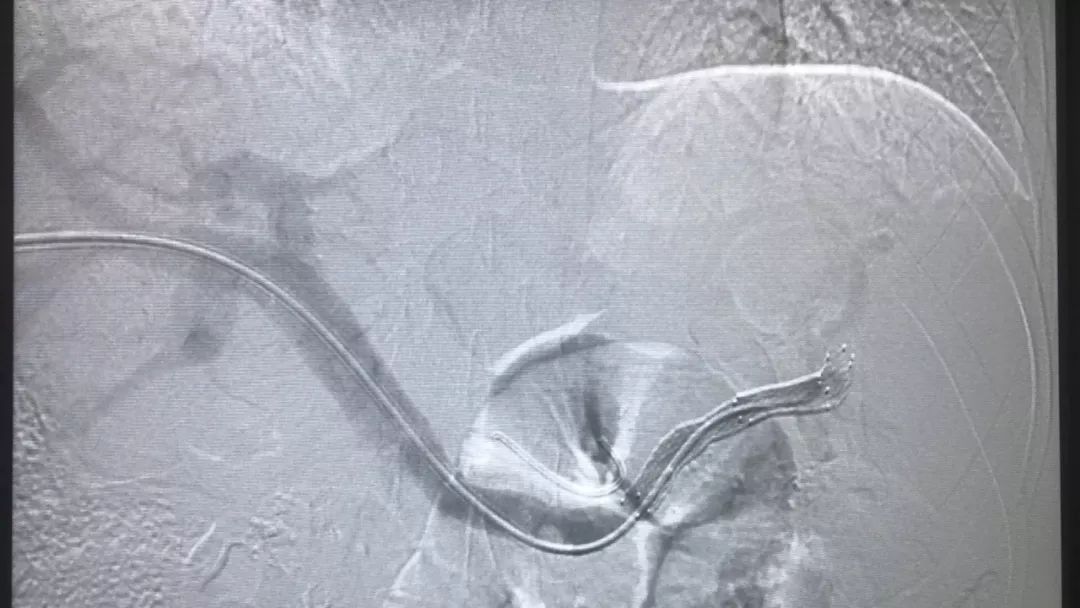

术中造影可见脾静脉闭塞,胃底静脉丛侧枝显影

支架开通后脾静脉通畅,侧枝静脉消失